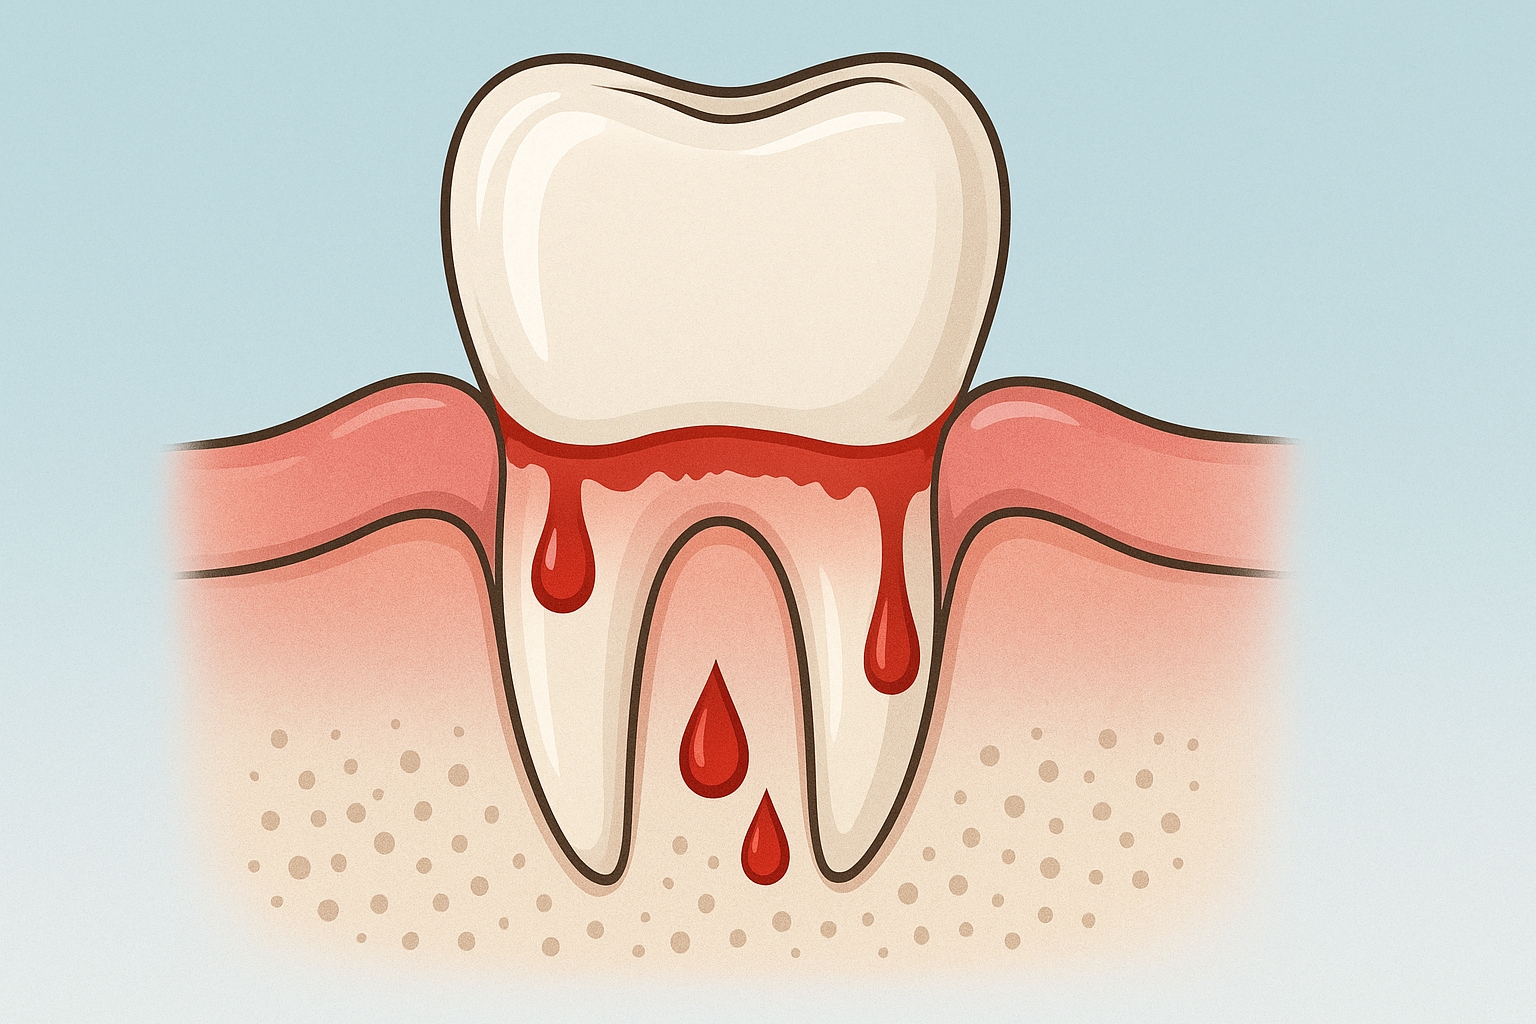

Przyzębie to zespół tkanek otaczających zęby – dziąsła, ozębna, cement korzeniowy oraz kość wyrostka zębodołowego. Kiedy dochodzi do ich stanu zapalnego, mówimy o chorobach przyzębia. Najczęstsze objawy to krwawienie dziąseł, nieprzyjemny zapach z ust, nadwrażliwość czy rozchwianie zębów.

Jeśli zauważasz krwawienie dziąseł, cofanie się linii dziąseł lub inne niepokojące objawy – nie czekaj. W IMDENTAL oferujemy profesjonalną opiekę periodontologiczną, dzięki której zadbasz nie tylko o zdrowie swoich zębów, ale i całego organizmu. Umów się na konsultację i przekonaj się, jak wiele możesz zyskać.